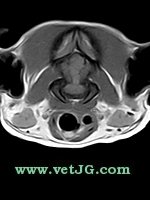

RESONANCIA MAGNÉTICA

AXIAL